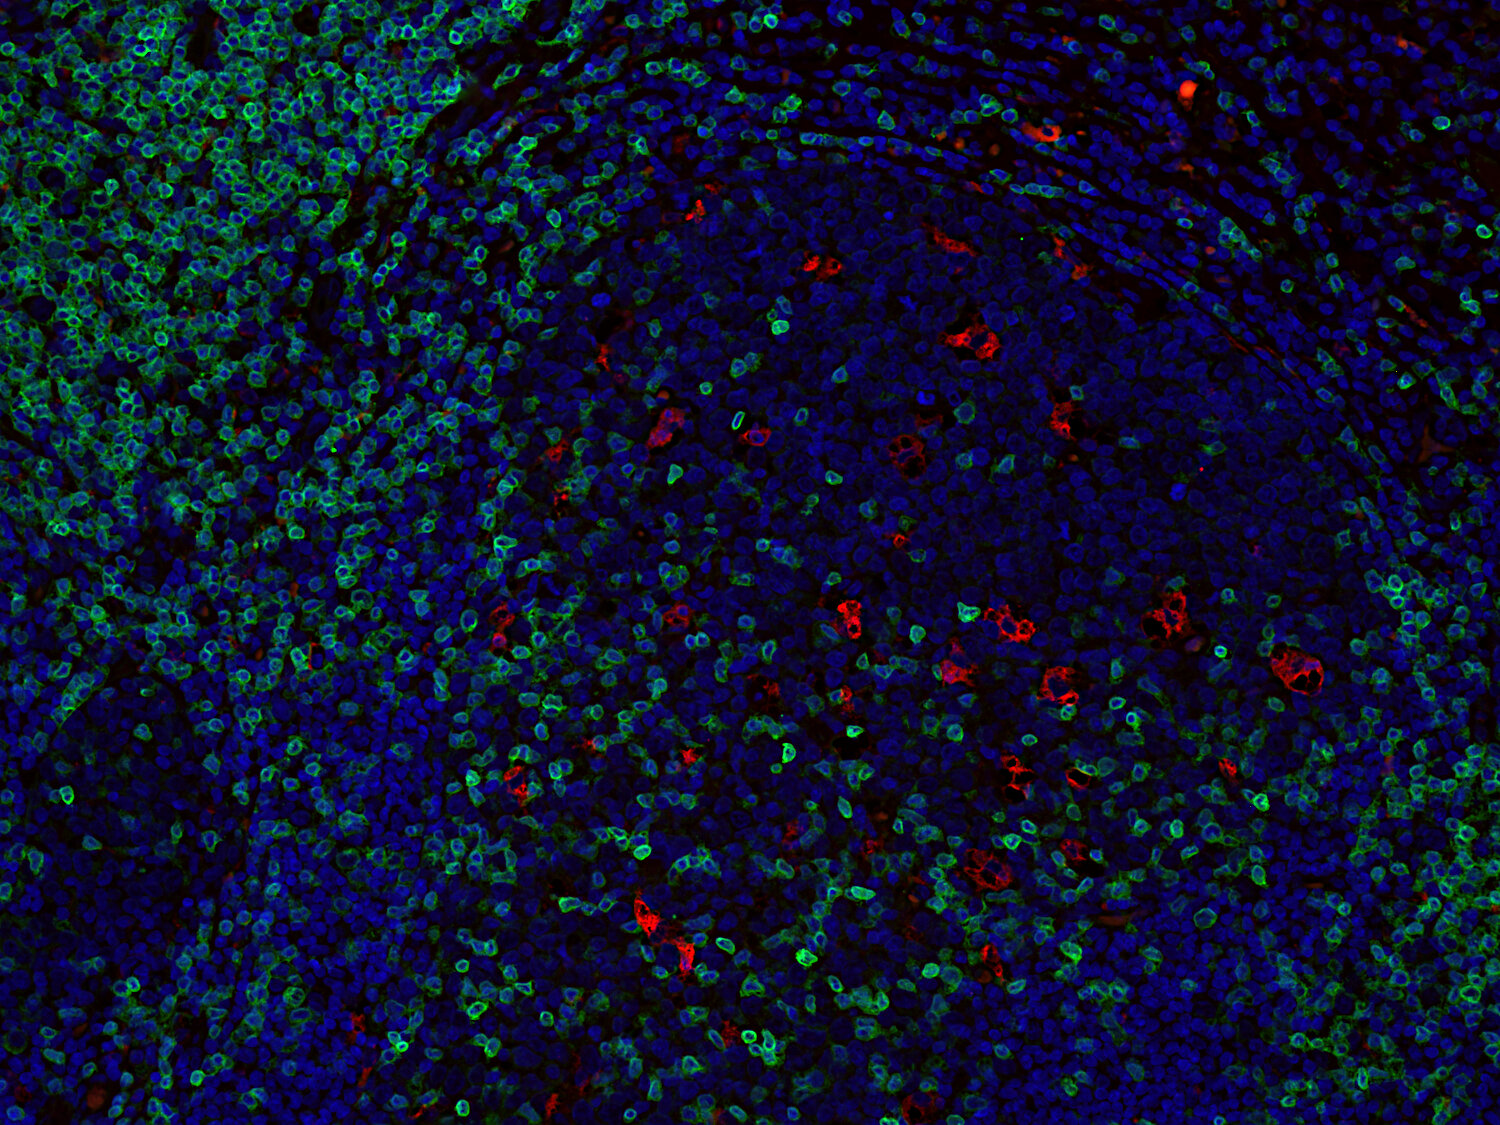

IHC-P: 1 : 1000 up to 1 : 4000 gallery

Immunohistochemistry (IHC-P) of formalin fixed, paraffin embedded (FFPE) tissue (some antibodies require special antigen retrieval steps, please refer to the ”Remarks” section). Immunoreactivity is usually revealed by fluorescence or a chromogenic substrate.

This product belongs to the HistoSure product line of antibodies developed for and extensively tested in FFPE tissues.

Cluster of differentiation 3 (CD3) is a defining feature of cells belonging to the T cell lineage. It is composed of the four subunits CD3 gamma, CD3 delta, CD3 epsilon (CD3e) and CD3 zeta, that form a multimeric protein complex. This complex associates with the T cell receptor (TCR) and serves as a T cell co-receptor. The CD3 molecules contain immunoreceptor tyrosine-based activation motifs (ITAMs) that serve as the nucleating point for the intracellular signal transduction machinery upon TCR engagement. TCR/CD3 signaling is central to the initiation of antigen-specific T cell responses to pathogens and vaccines, as well as transplanted tissues, tumors, and autoantigens. CD3 is initially expressed in the cytoplasm of pro-thymocytes. During T cell maturation the expression of CD3 migrates to the cell-membrane. The specific appearance at all stages of T cell development make CD3 a useful immunohistochemical marker for T cells in tissue sections. In the clinical setting, CD3 is a relevant marker for the classification of malignant lymphomas and leukemias as the antigen remains present in almost all T-cell lymphomas and leukemias. It can also be used to detect T cells in celiac disease, lymphocytic and collagenous colitis.